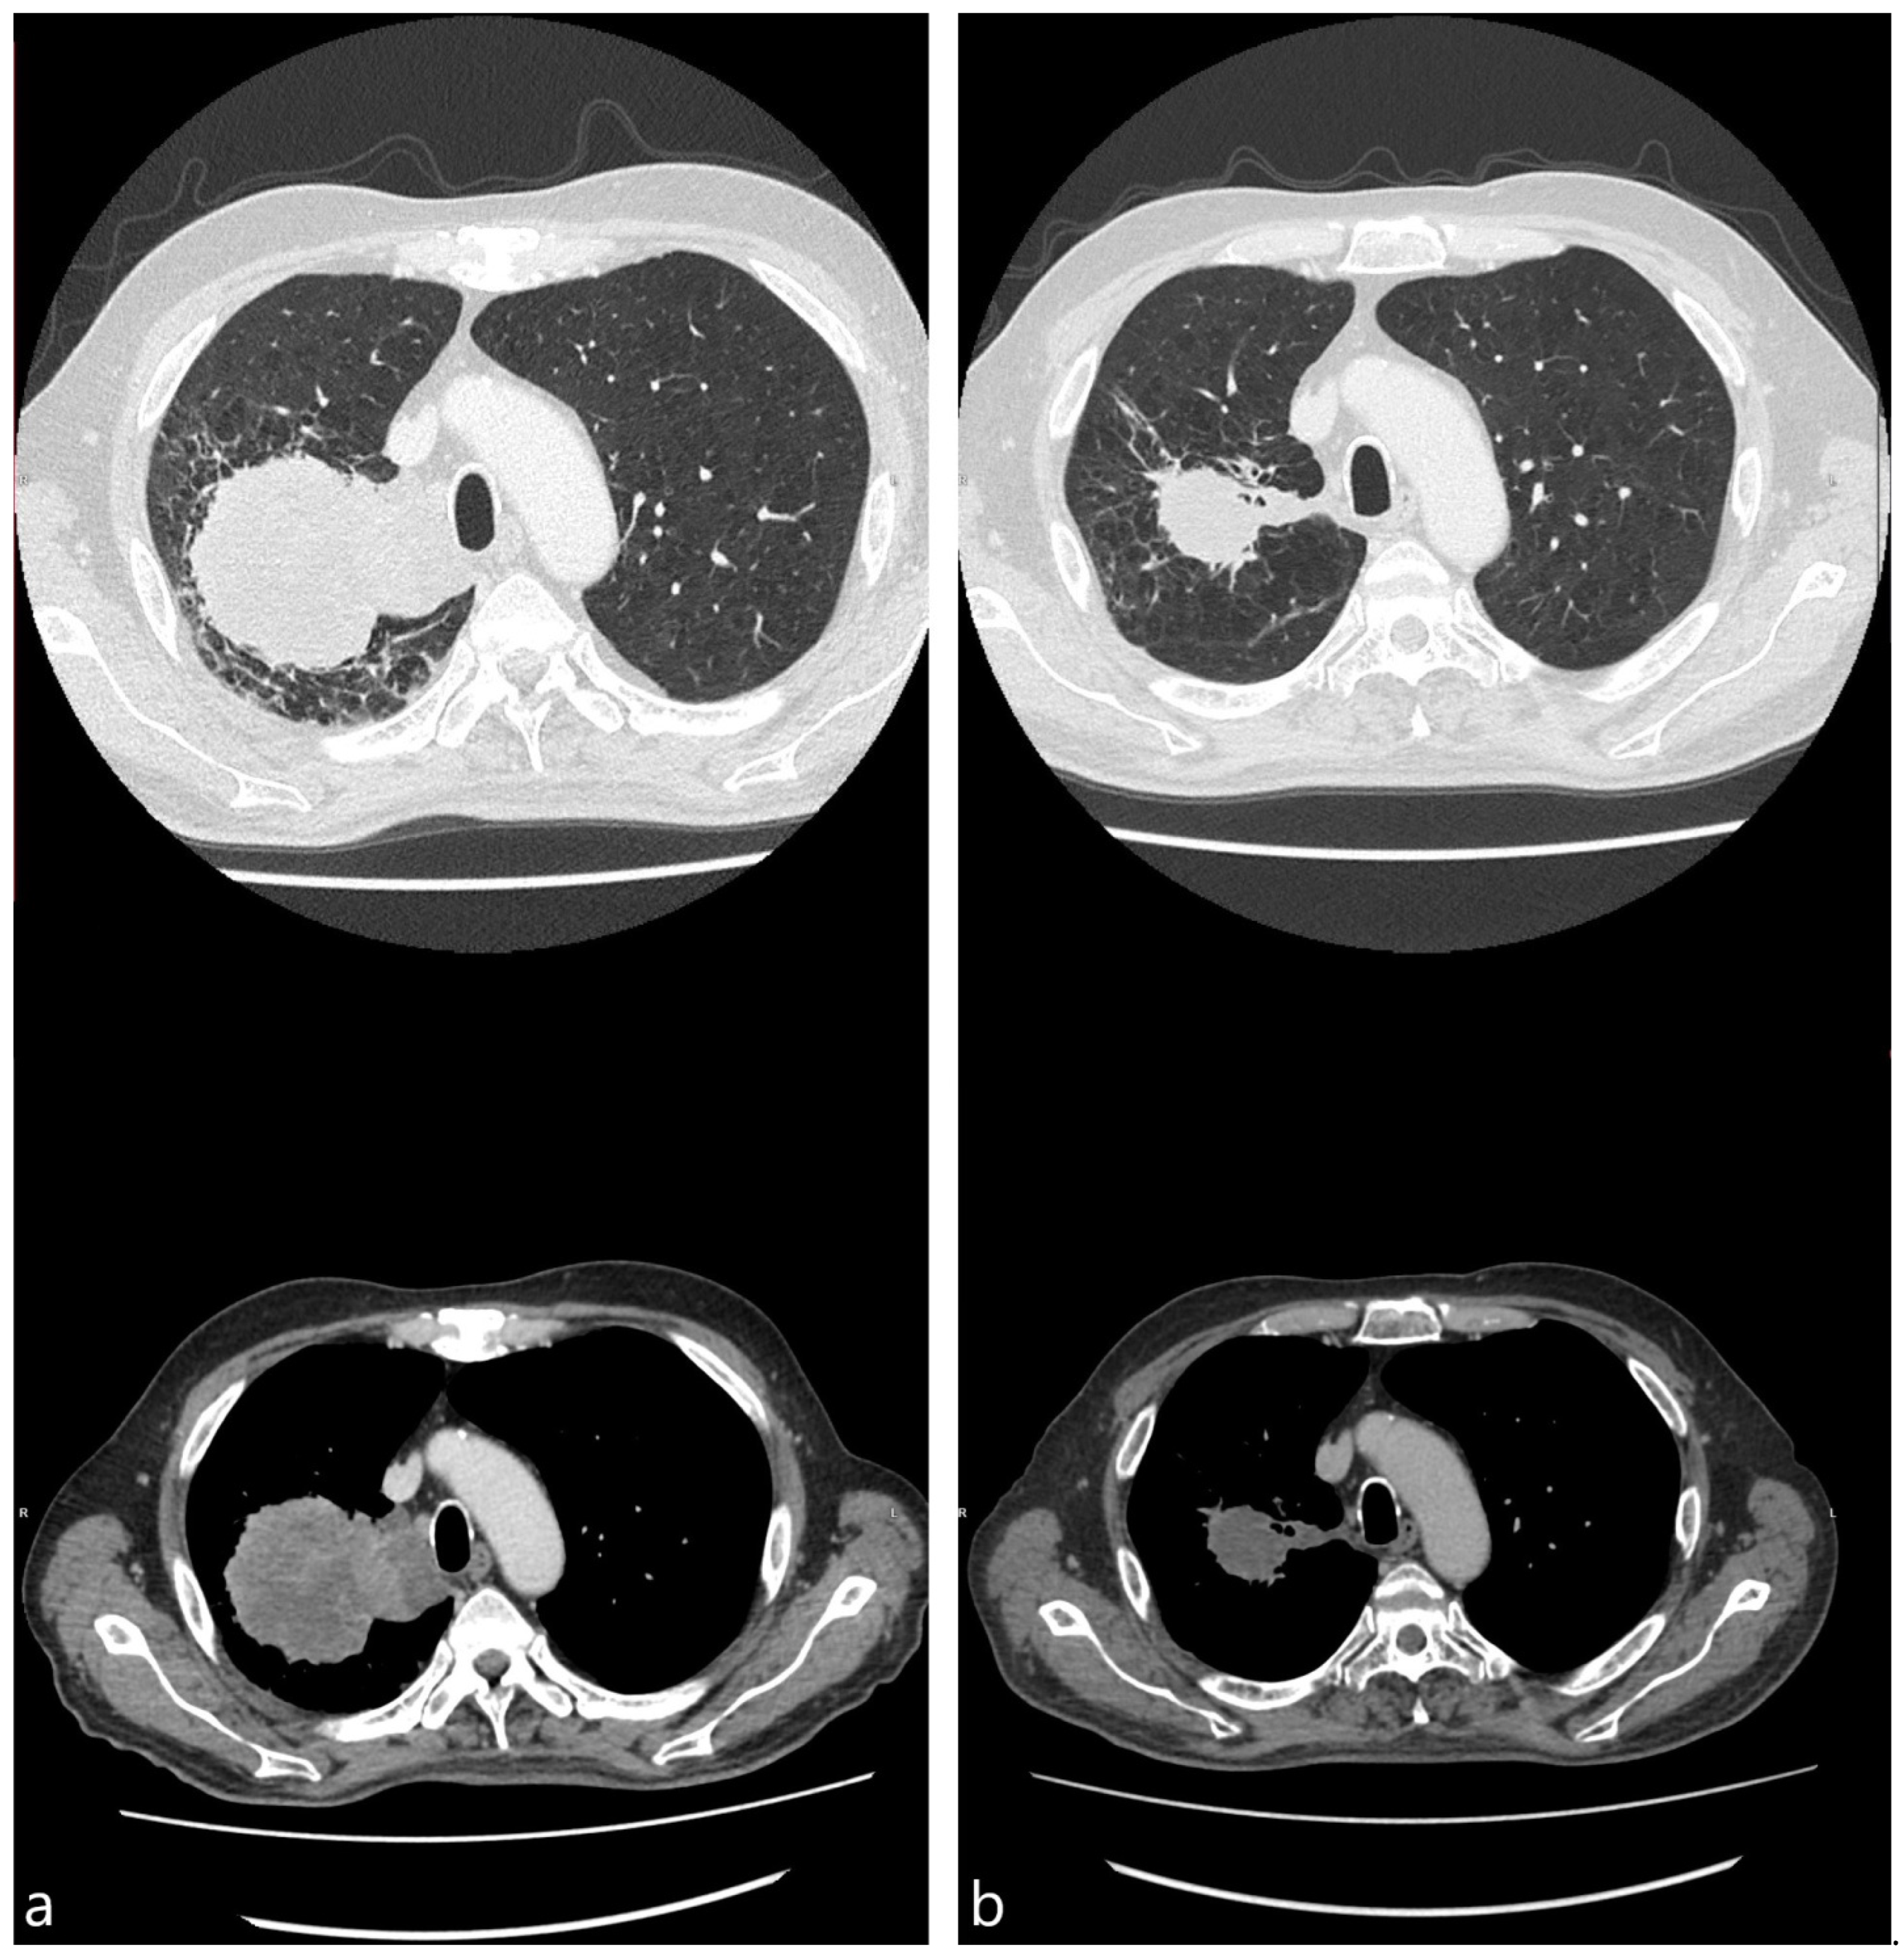

The median surface area of the treated tumors showed continuous shrinking from the baseline to the time of the fourth cycle, measuring 22.4 (10.1–62.3), 14.4 (10.6–26.6), and 10.2 (6.1–19.1) cm2 (p < 0.001). Additionally, 3 out of 20 (15.0%) patients had signs of cavitation in the tumor treated with cryotherapy at the baseline. This number increased to seven (35.0%) and eight (40.0%) during subsequent scans. Meanwhile, necrosis was observed in 12 (60.0%), 13 (65.0%), and 8 (40.0%) patients at the baseline, second, and fourth cycles, respectively. A pair of representative cases showing tumor reduction and cavitation are shown in Figure 2 and Figure 3.

Figure 2.

CT images, obtained 1 week before (a) and 4 weeks after (b) bronchoscopic cryotherapy (59 y.o. female with stage IV squamous cell carcinoma, PD-L1 expression 3%).